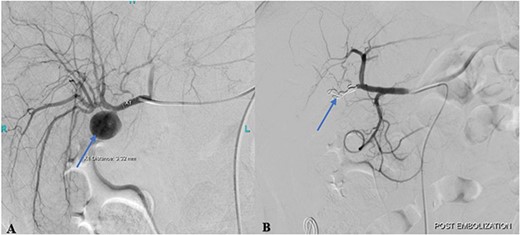

Cannulation of the celiac and superior mesenteric arteries were performed using a 4 French C1 Catheter to perform an angiogram. The angiogram showed a saccular aneurysm measuring 23 × 21 mm arising from the right hepatic artery just at the origin of the cystic artery stump (Fig. 2A). After considering multiple options, it was decided to embolize the hepatic artery proximal and distal to the aneurysm using the jail technique. Selective cannulation of the right hepatic artery was performed with a catheter tip placed distal to the origin of the aneurysm using a Progreat microcatheter. The distal segment was then embolized using three steel coils. The microcatheter was then retracted, proximal to the aneurysm origin followed by proximal segment embolization using three steel coils.

(A) Pre-embolization angiogram of the hepatic artery demonstrates pseudoaneurysm of the cystic artery stump (arrow). (B) Post-coil embolization angiogram of the hepatic artery shows no further filling of the pseudoaneurysm (arrow).

Post-procedural angiogram showed a complete occlusion of the aneurysm and satisfactory filling of the right lobe of the liver through its collaterals from the left hepatic artery (Fig. 2B). Post-procedure hospital stay was unremarkable for any procedure-related complication or hospital-acquired infection. The patient was discharged on the 3rd post-procedure day in stable condition with no output from the abdominal drain.